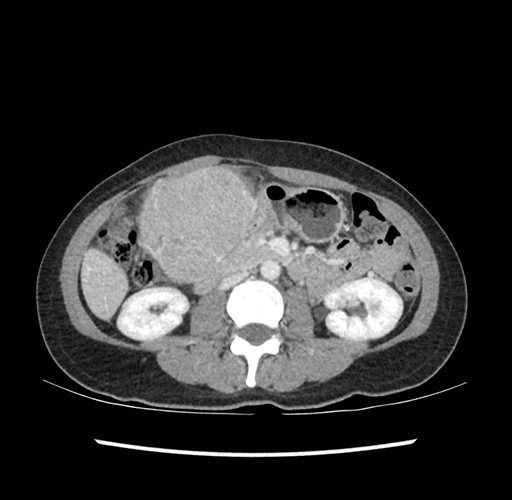

Imaging Analysis

Look through the patient's CT scan to identify any areas of concern for the necessary procedure.

Based on your CT findings, which issue(s) would give reason for "planned slowing down moment(s)" in this case?